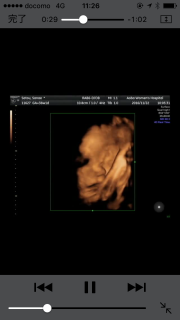

写真:36w1d:かなえさん:大腿骨

36w1d 推定2384g